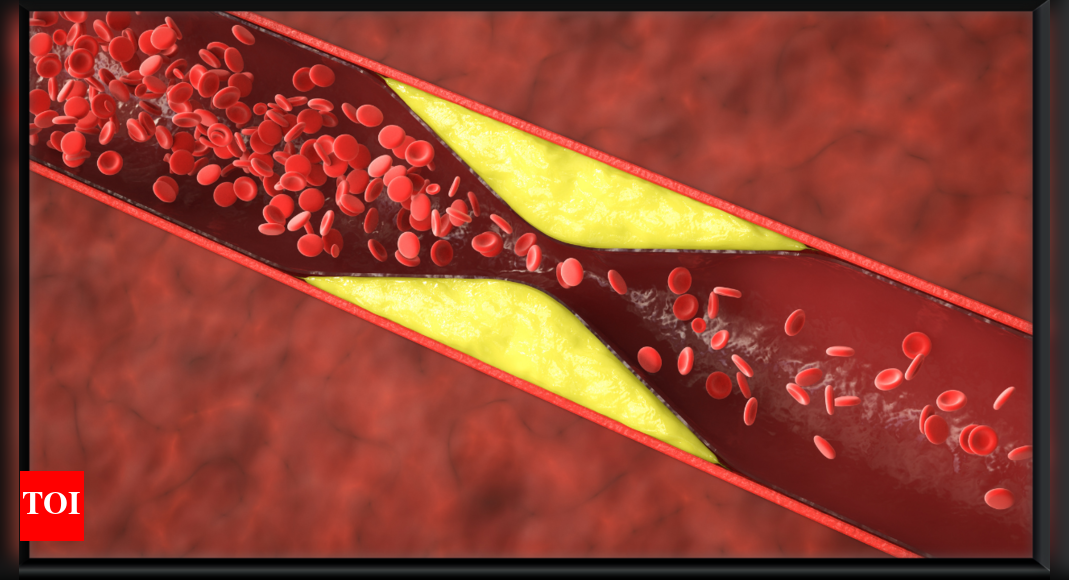

High cholesterol is commonly referred to as a “silent killer.” Unlike other medical conditions, it does not have noticeable symptoms in the early years. In its early stages, there are no specific symptoms. Many people live for years with dangerously elevated cholesterol levels, unaware of the harm quietly building within their arteries. But though it might not be yelling for help, the body sometimes sends some subtle signals.That said, cholesterol-related complications can manifest in subtle, silent ways—often misattributed to other causes. Recognizing these early clues may help prevent serious events like heart attacks or strokes. These are five silent warning signs that may be trying to alert us.

Leg pain while walking (Claudication)

If you experience odd pain or cramping in your legs when walking or climbing stairs, it could be more than tired muscles. This symptom, known as claudication, is commonly associated with peripheral artery disease (PAD)—a condition in which cholesterol deposits narrow the arteries supplying the limbs with blood. It usually decreases with rest but returns with activity. PAD is a red alert for extensive arterial damage due to high cholesterol.